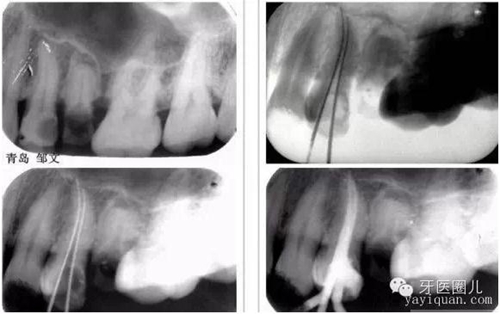

1.確定工作長度(根測(cè)儀+X光片)這個(gè)大家都知道就不再贅述

觀察術(shù)前X光片,設(shè)想達(dá)到一個(gè)理想的結(jié)果,然后用這一設(shè)想來指導(dǎo)每一治療步驟,這樣自然會(huì)提高我們的根管治療的操作水平。

患者外傷11 21簡單冠折,選擇一次法完成冷牙膠充填3天后行樁修復(fù)。

一次法充填后最嚴(yán)重的疼痛發(fā)生在治療后24小時(shí)內(nèi),也有文獻(xiàn)說是6-8個(gè)小時(shí),隨后患者反應(yīng)會(huì)大大減輕,與多次法比較治療的并發(fā)癥和成功率沒有差別,這個(gè)病例次日電話回訪患者患者無不適。